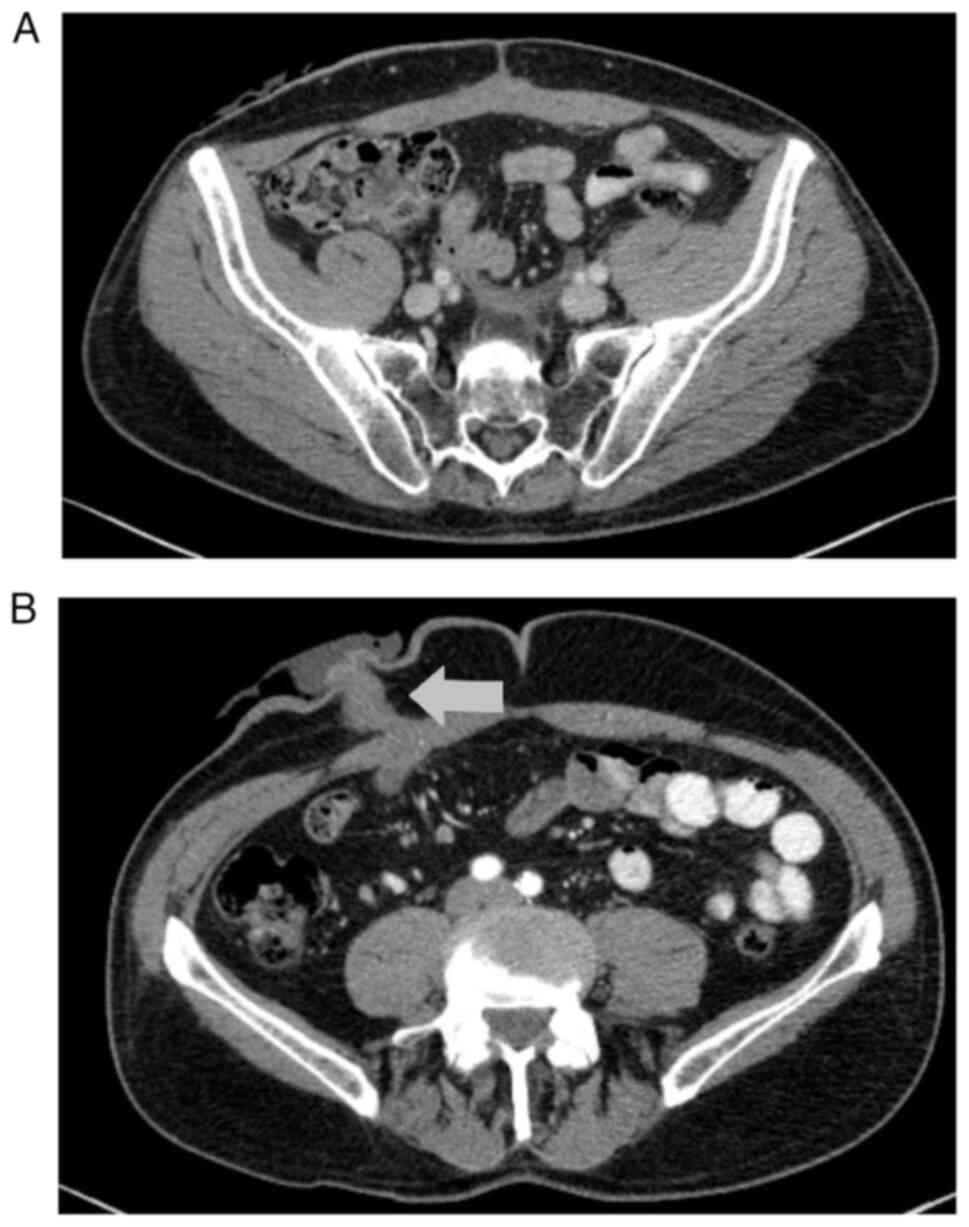

The postoperative histopathological examination showed high-grade pT3a urothelial carcinoma of the urinary bladder. The first postoperative CT scan showed no local recurrence and no lymphadenopathy or metastases in the parenchymal organs or bones (Fig. 2). The patient remained under observation with no signs of progression of the disease. Regular CT scans were performed every 3 months and other supportive examinations were performed as part of the oncological follow-up. In March 2023, the patient was readmitted to the Department of Urogenital Cancer at the Maria Skłodowska-Curie National Research Institute of Oncology (Warsaw, Poland) for suspected uretero-enteric strictures and bilateral hydronephrosis. The patient qualified for surgical treatment. The last CT scan before the planned surgery (performed in January 2023) revealed no recurrence or metastasis of urothelial carcinoma. Laparotomy was performed, during which an inflammatory infiltration was found intraoperatively, absorbing the junctions of the ureters with the Bricker loop and the appendix. The appendix was located in close proximity to the Bricker loop, but not in direct contact with it; the surrounding tissues were inflamed. This finding suggested appendicitis accompanying the ureteral strictures. Macroscopically, there was no suspicion of cancer recurrence. The ureters were resected and implanted into the Bricker loop. The inflamed appendix was removed and submitted for histopathological examination, which revealed neoplastic cells arranged in irregular nests or single cells within the subserosal connective tissue (Fig. 3). Neoplastic cells showed high-grade nuclear features, such as nuclear pleomorphism, hyperchromasia, a high nuclear-to-cytoplasm ratio and mitotic figures (Fig. 4). The following immunoprofile was observed: p40d (+), cytokeratin (CK)AE1/AE3 [CKAE1/3 (+)], CK high molecular weight (+), CK5/6 (+), CK20 (−), CK7 (−), caudal-type homeobox transcription factor 2 (−), GATA binding protein 3 [GATA-3 (+)], S100 calcium binding protein P (−), Uroplakin III (−), insulinoma-associated protein 1 (−), Synaptophysin (−), Chromogranin (−), prostate-specific acid phosphatase (−) and antigen Ki-67 [Ki-67 (+)] with ~30% positive nuclei (Fig. 4, Fig. 5, Fig. 6, Fig. 7, Fig. 8, Fig. 9A). A pronounced retraction artifact was present; therefore, vascular invasion was excluded by immunohistochemistry [CD34 (−), CD31 (−); Fig. 9B and C]. All immunohistochemistry protocols were performed according to the instructions of the manufacturer and staining platforms. The details of all antibodies used are provided in Table I. Ultimately, the neoplasm's morphology, in correlation with immunohistochemical results, corresponded to a cancer metastasis to the appendix, primarily of urothelial origin. The differential diagnosis included colorectal cancer, neuroendocrine neoplasms and prostate cancer.

Figure 2.

First postoperative CT scan. (A) No local recurrence, no lymphadenopathy, no metastases in the parenchymal organs or bones. (B) The arrow indicates the Bricker loop.